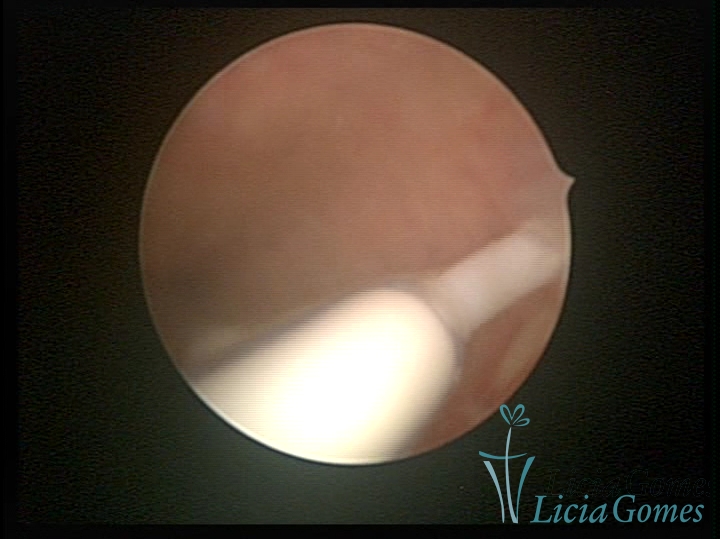

Normoinserted IUDo

×

Normoinserted IUD